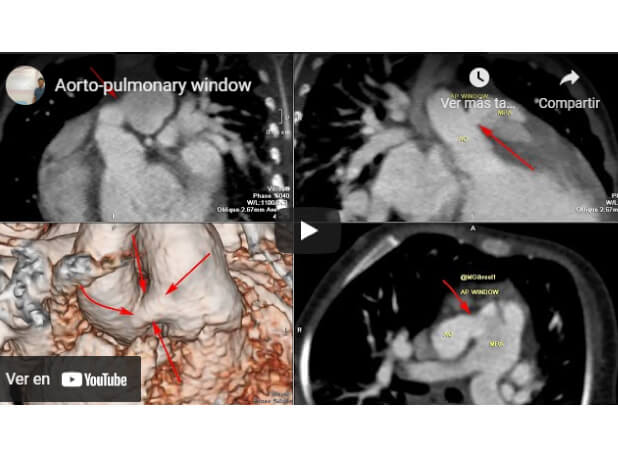

Aorto-Pulmonary Window

Mohamed Gibreel , FEBR (Fellowship of Egyptian Board of Radiology ) Cardiac imaging consultant at Aswan heart center -Magdi Yacoub Foundation , Egypt